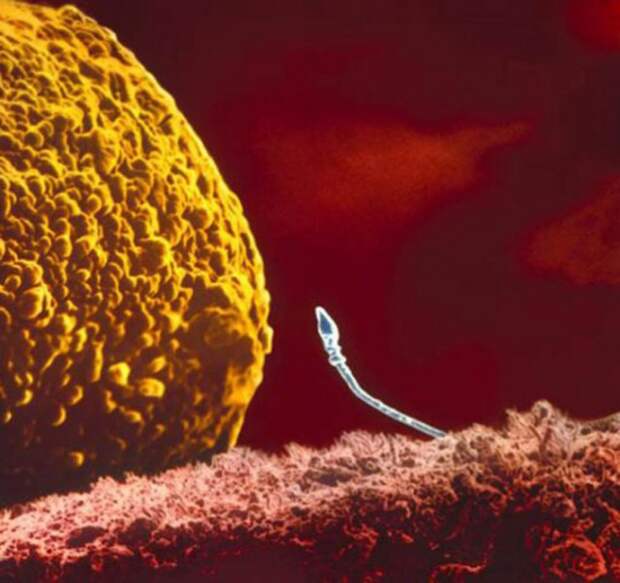

2. Яйцеклетка.

3. Судьбоносная встреча.